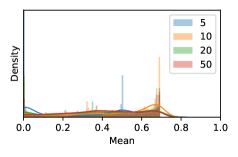

To model how different classifiers will respond to a given input , we assume that the prediction from classifier is sampled from a beta distribution that is characterized by two parameters by and . We further assume that is fixed to the same constant value for all ’s. Under this assumption, each input can be described by ( can be calculated since is fixed), easing further analysis. The Severity Level (SL) of the case represented by image can be characterized by the parameter . The larger the value of , the more severe the case of is. When and are close, the case is ambiguous as the distribution shifts towards being symmetric (i.e. signifying much disagreement among classifiers) rather than being one-sided (i.e. consensus among classifiers that is negative or positive). We provide a set of examples in Figure 2 and also Figure S.8 in the supplementary materials showing how the beta distribution can be used to capture diverse predictions given by an ensemble learner.

In contrast, the MC-dropout method showed the worst overall performance among the three, as it can be seen from the high ratios of SL0 examples among the uncertain negatives in Figure 4. The histograms in Figure 2 provides another perspective to look into the phenomenon, where a decent proportion of MC-dropout model’s predictions on SL0 inputs entailed low confidence (far from 0 or 1), which from another angle explained why MC-dropout was less specific in terms of lower FNP; many no-DR inputs (i.e. SL0) were erroneously assigned high uncertainty by MC-dropout models.

As discussed in Section 5.1 and Section 5.3 in the main paper, the mean metric and the stacking ensemble will have better performance in the precision (specificity) on the ambiguous data. Here, more detailed results are shown in Figures S.3 & S.6 and Table S.1. Figures S.3 & S.4 show the histograms of the uncertainty score for Kaggle-DR and Messidor-2 datasets that are the in-distribution (i.d.) dataset in our experiment and FigureS.5 & S.6 show the histograms for ImageNet and CIFAR-10 datasets, which is the o.o.d. datasets in our experiment. Each group of histograms contains results from the three evaluated ensemble methods (stacking ensemble, MC-dropout and TTA) and the three uncertainty metrics (mean, var and kl). Additional detailed results not displayed in Figure 4 can be found in Table S.1, which shows the proportion of the data of different SLs varies across different . For comparison, we also included in Table S.1 the results from single learners, and the proportions of data of different SLs (before any selection was made).